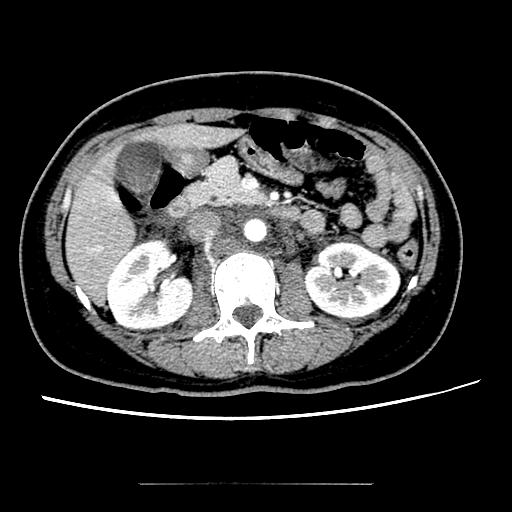

请教大家,这个注入下腔静脉的是什么血管??该期是打针后30s扫描的图像。

椎旁静脉直接汇入下腔静脉.

注意哦,这个是动脉期

下腔还没有显影,怎么会椎静脉有,而下腔没有造影???

我决得你的图像太少了>门脉期大概是25~``~28考虑是不是门脉和胸壁的异常交通支啊?这位患者有无肝硬化?